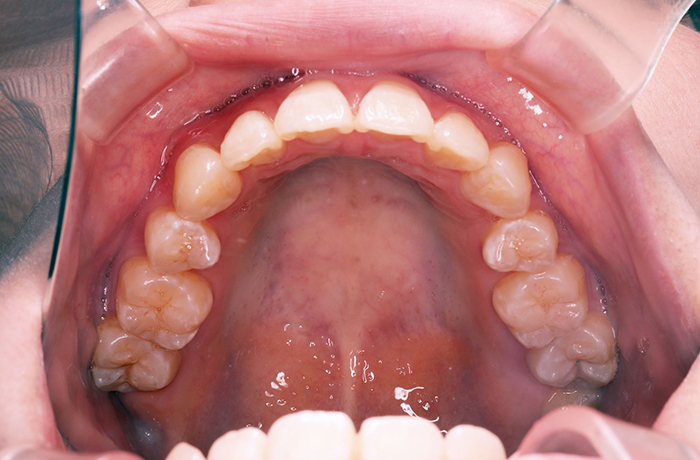

治療後

after

患者の症状 叢生、正中のずれ、上顎左右側切歯の口蓋側転位(交叉咬合)

治療方法 非抜歯で、マウスピース型カスタムメイド矯正歯科装置(インビザライン)による矯正

歯列弓を拡大することで非抜歯を可能にしました。

治療結果 側切歯の交叉咬合は解消、上下正中のずれも改善し咬み合わせが良くなりました。